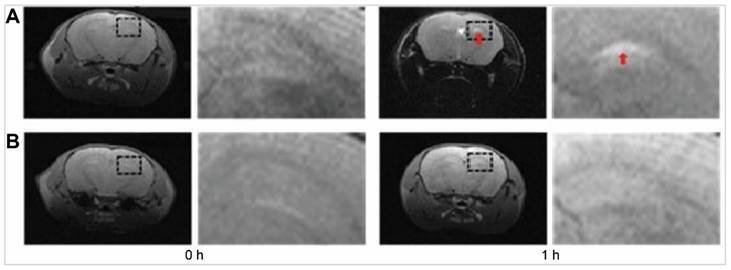

In 2012, Mustafa et al. assessed the IN administration of lipophilic [99mTc]-labelled ropinirole to the brain in rabbits through the olfactory pathway using NE and its homogenised version [33]. The focus was on the fate of these formulations in the CNS. Brain bioavailability was assessed using gamma scintigraphy in a dynamic model involving radiolabelled nanoformulations of [99mTc]-NE-ropinirole and [99mTc]-suspension ropinirole. The study highlighted the superior brain localisation and Cmax achieved with [99mTc]-NE-ropinirole compared to [99mTc]-suspension ropinirole, suggesting that the formulation is directly transported from the nasal cavity into the CSF, bypassing the BBB. Comparative dynamic mobility of the different formulations of [99mTc]-NE-ropinirole and [99mTc]-suspension ropinirole was performed by IN administration in rabbits for 30 min. Continuous imaging of the head was performed to track drug mobility from nose-to-brain and systemic circulation. The imaging revealed that the maximum residence time in the nasal cavity was not more than 10 min, likely due to mucociliary clearance. After 15 min, the drug was almost entirely cleared from the cavity, but a clear black signal was observed in the head region, indicating brain uptake. The imaging analysis revealed a faster onset of action, with the optimised homogenised NEs achieving a Tmax at ~6.7 min post-IN administration, whereas [99mTc]-suspension ropinirole had a Tmax at ~11.7 min. Homogenisation was found to significantly improve brain uptake of ropinirole, underscoring its potential in enhancing CNS drug delivery. The enhanced brain delivery is attributed to the lipophilic nature of the NE carriers, and the smaller size facilitated faster absorption through the olfactory neurons, a crucial factor in overcoming mucociliary clearance, which is a significant challenge in INDD. The suspension form, being less effective, highlights the importance of the formulation's physicochemical properties in biodistribution and efficacy in the nose-to-brain pathway. Moreover, due to the fast absorption and low dose volume, there was minimal escape of therapeutic molecules to the systemic circulation, resulting in low systemic bioavailability.